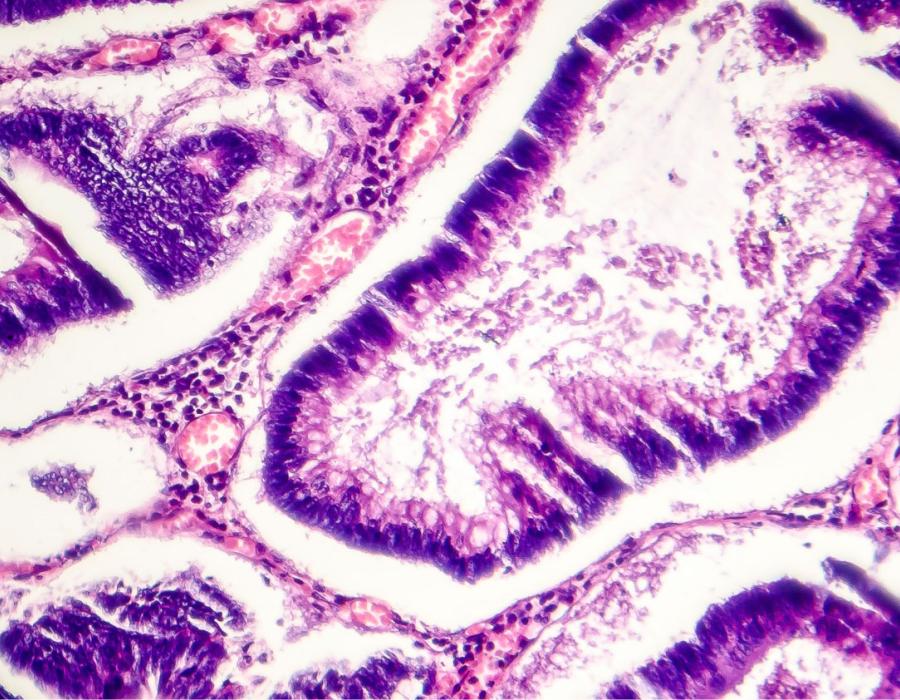

Polyps are tissue growths inside the colon or rectum that are generally benign but can develop into cancer if they are allowed to grow. Some types of polyps can change into cancer over time (usually many years), but not all polyps become cancer. The chance of a polyp turning into cancer depends on the type of polyp it is.

There are three different types of polyps that can be found inside the colon or rectum with colonoscopy2:

- Hyperplastic polyps and inflammatory polyps: Most common polyps, generally not pre-cancerous.

- Adenomatous polyps (adenomas): Can change into cancer and because of this are called a pre-cancerous condition.

- Sessile serrated polyps (SSP) and traditional serrated adenomas (TSA): Often treated like adenomatous polyps and removed during a colonoscopy because they also have a high risk of developing into colorectal cancer